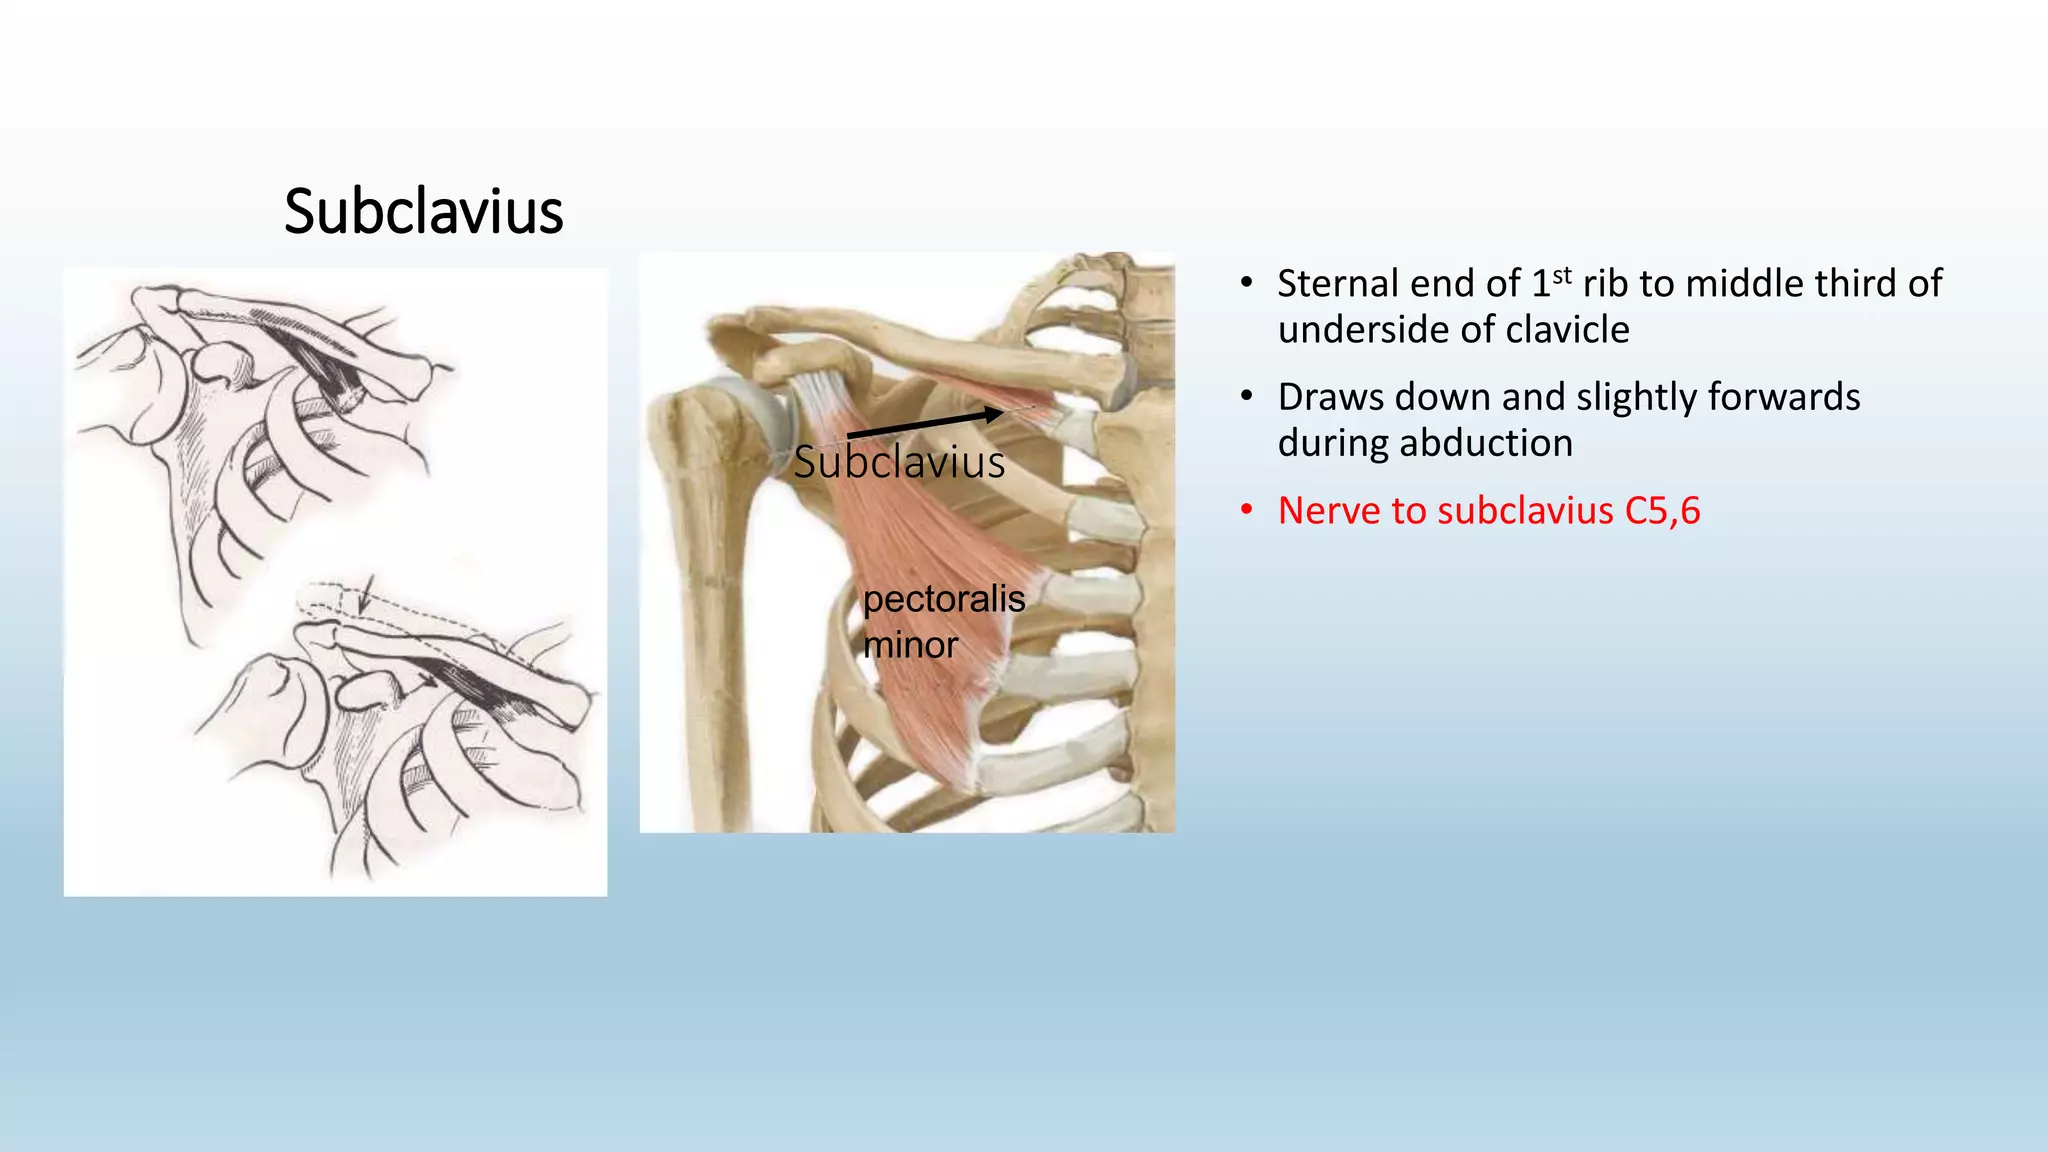

The document summarizes an anatomy revision session on the upper limb. It discusses various muscles of the upper limb including their origins, insertions, innervations and functions. Key muscles covered include the pectoralis major and minor, serratus anterior, deltoid, biceps brachii, brachialis, coracobrachialis, and triceps. It also discusses the rotator cuff muscles and muscles of the forearm including flexor carpi ulnaris and radialis. The session aims to help students identify upper limb muscles and understand their relations to nerves.